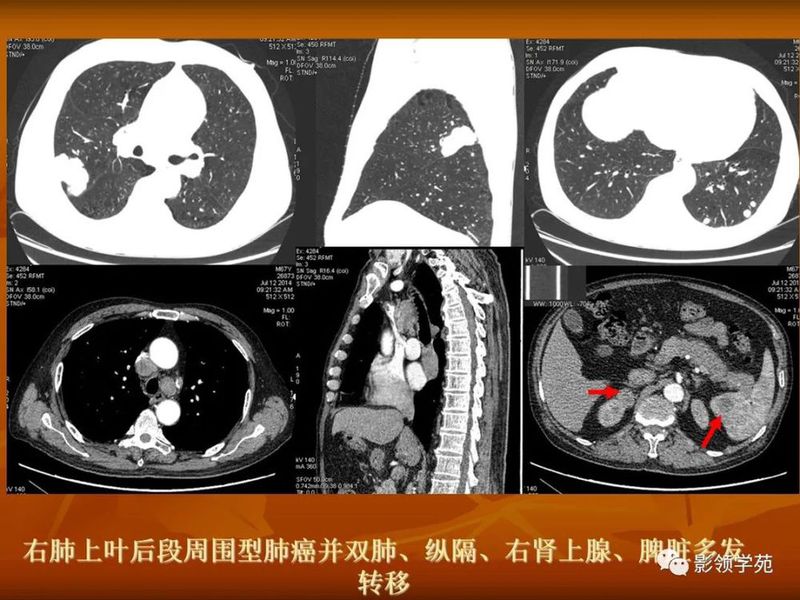

(1)较大含空洞性肿块,洞壁较厚,大于15mm,空洞外壁有分叶、毛刺,洞壁凹凸不平有壁结节,增强可见不规则强化,周围未见明显卫星病灶时,首先考虑周围型肺癌;癌性空洞洞壁一般肺门侧较厚,空洞多偏于外侧,伴有同侧淋巴结肿大更支持肺癌诊断。